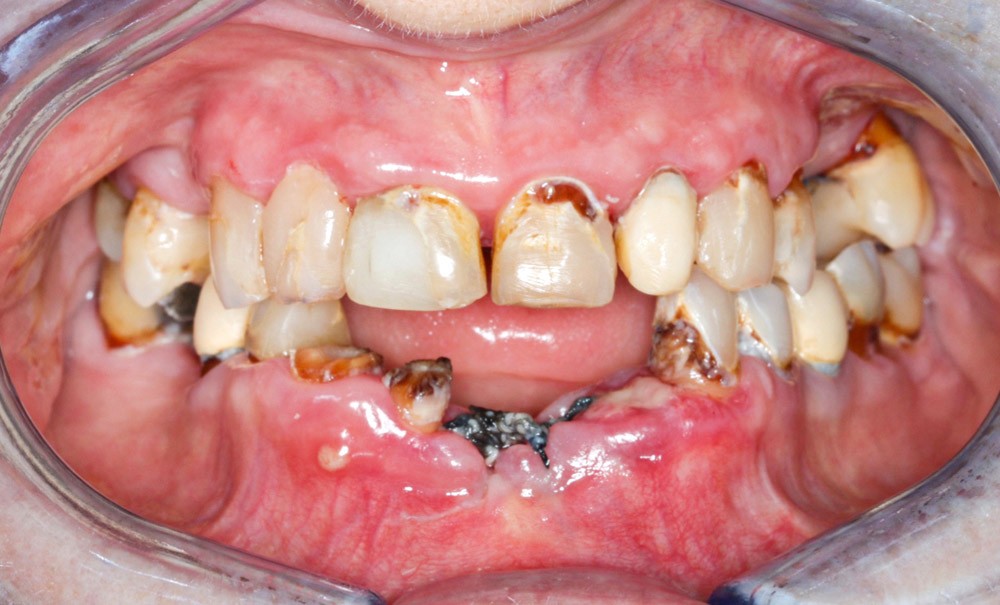

C’est donc à travers la description du parcours thérapeutique d’une patiente caucasienne de sexe féminin âgée de 63 ans, non-fumeuse et souffrant de troubles bipolaires que nous avons souhaité illustrer l’importance d’une prise en charge adaptée pour les personnes souffrant de maladies mentales sévères.

Première consultation au centre de soins dentaires en mai 2020 sous motif d’une « mobilité » des incisives centrales inférieures. La patiente ne se plaint pas de douleurs, mais souhaiterait bénéficier d’une prise en charge complète, restauratrice et esthétique. Elle prend quotidiennement…